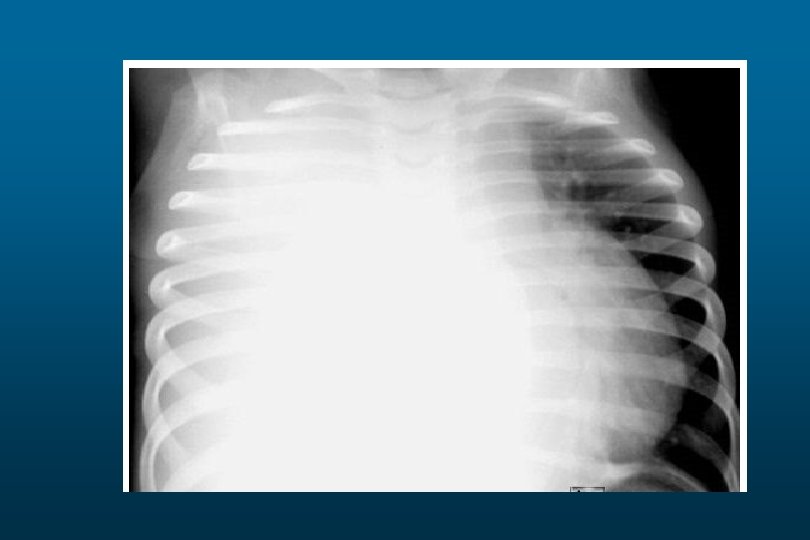

RDS